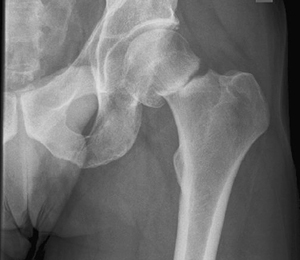

Принципи лікування остеопоротичних переломів

2. Класифікація остеопоротичних переломів

3. Механіка утворення остеопоротичних переломів